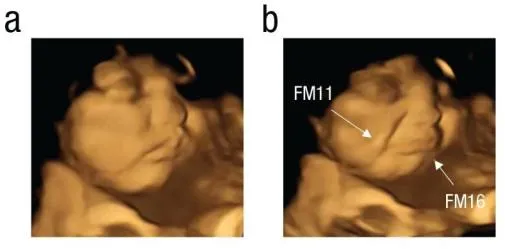

英国杜伦大学研究团队

一项关于胎儿口味好恶的研究

获得2024菠萝科学奖“医学奖”

实验让100名孕妇吞下装有

胡萝卜粉末或者羽衣甘蓝粉末胶囊

通过4D超声波扫描

进行观察记录发现

妈妈吃下胡萝卜的胎儿

会露出笑容

而吃下羽衣甘蓝的胎儿

直接带上了“痛苦面具”

妈妈吃过胡萝卜的胎儿↑

妈妈吃过羽衣甘蓝的胎儿↑